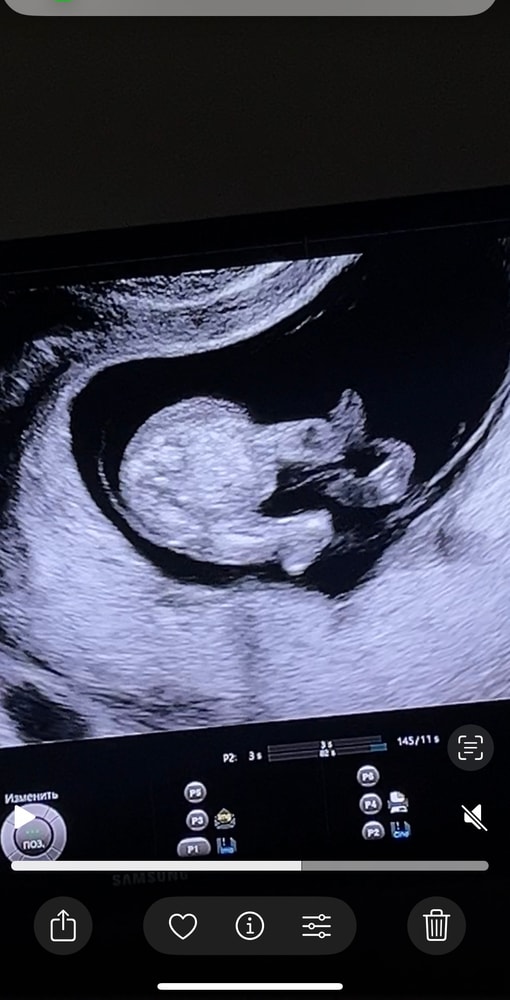

По узи срок 13 недель. 3 фотка предположили, что мальчиковые половые органы, на 1/2 фотке ничего вроде бы не видно(только пуповина). Как думаете узист ошиблась? Хотя уверена вроде говорила… Оч хочу дочу, снилась мне вчера, а тут я ошарашена новостью. Девочка до беременности снилась и я прям чувствовала, что мне надо за ней. Решилась как видите на 1 беременность и тут такое. У вас путали с пуповиной пол? Поделитесь своими историями…